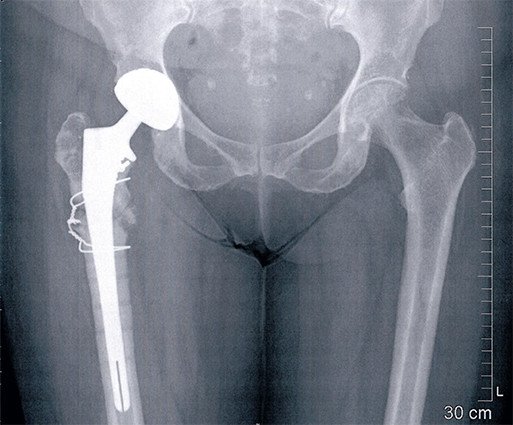

Pseudoarthrose nach Femurfraktur

Diese 70-jährige Patientin zog sich vor 10 Jahren eine Fraktur des Schenkelhalses rechts zu, welche operativ versorgt wurde. Vor einem Jahr wurde das Osteosynthesematerial dann entfernt. Es kam zu einer erneuten Fraktur, an einer anderen Stelle des Oberschenkelknochens, auch dieses Mal wurde eine Osteosynthese durchgeführt. Es kam jedoch zu einem Versagen dieser Osteosynthese mit Ausriss der Schrauben und einer fehlenden Heilung in der Fraktur. Dies wird als Pseudoarthrose bezeichnet. Da eine nochmalige Osteosynthese schwierig, risikoreich und bezüglich des Resultates ungewiss gewesen wäre, haben wir uns zur Implantation einer Hüfttotalprothese entschieden.

Hierbei wurde ein längerer Schaft verwendet, welcher den oberen Anteil des Oberschenkelknochens auffädelte und so die Stelle des fehlenden Durchbaus überbrückte. Es gelang so eine stabile Situation herzustellen. Die Patientin ist entsprechend wieder mobil und beschwerdefrei gehfähig.